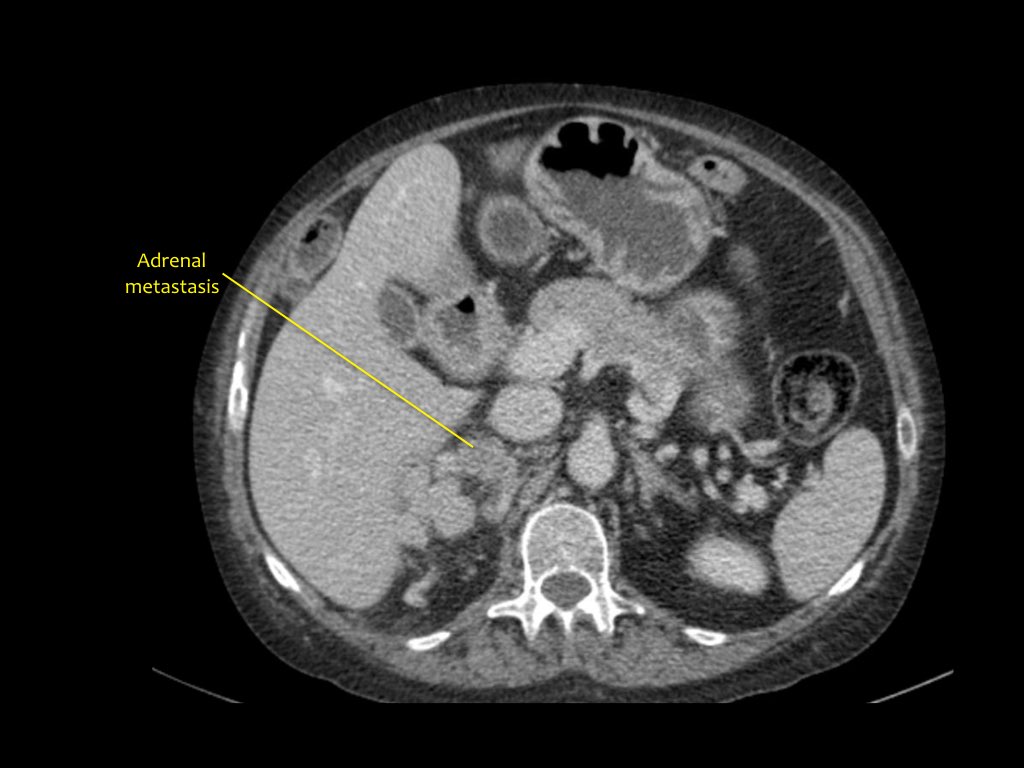

Phân giai đoạn RCC

RCC có thể xâm lấn mỡ quanh thận vượt qua cân thận và có thể lan vào tĩnh mạch thận, tĩnh mạch chủ dưới (IVC) hoặc tuyến thượng thận cùng bên.

Đối với phẫu thuật viên, điều quan trọng là cần biết có huyết khối u trong IVC hay không và liệu huyết khối có lan vào lồng ngực trên cơ hoành hay không (cần có phẫu thuật viên lồng ngực trong ca mổ).

Khoảng 25% bệnh nhân đã có di căn tại thời điểm chẩn đoán.